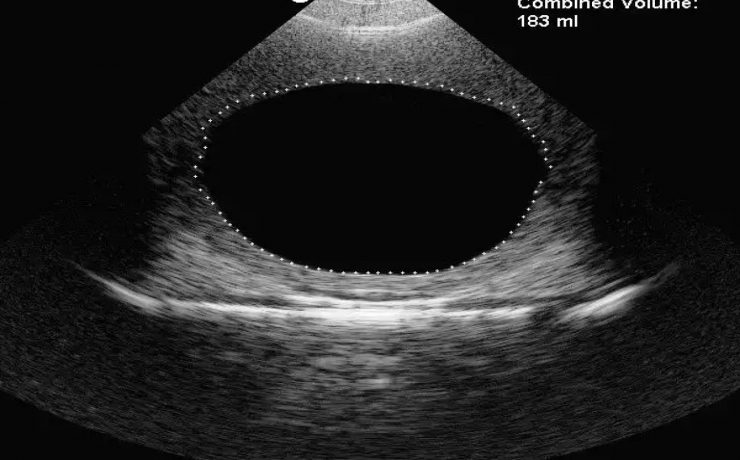

Este es un artículo de revisión publicado por el Departamento de Ginecología y Obstetricia del Hospital William Beaumont, Oaklahoma USA. La placenta accreta con sus variantes increta y percreta son una causa importante de hemorragia en el segundo y tercer trimestre de gestación representando hasta el 50% de las histerectomías